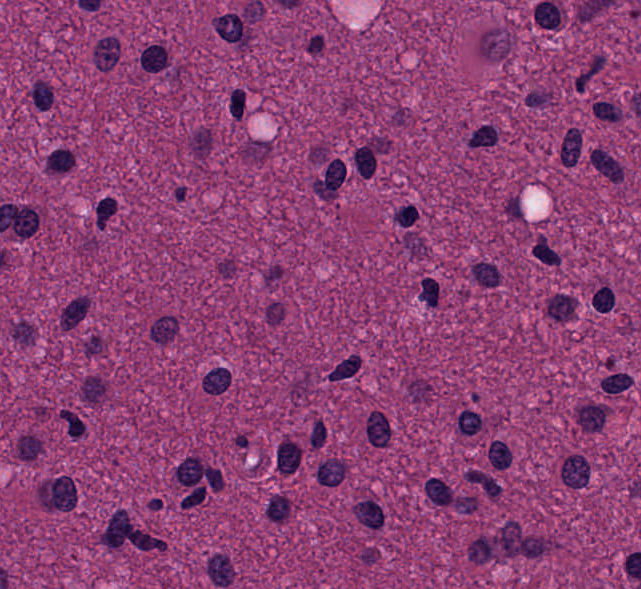

Input images sample variability

Overview

Differing Saliency

- some nucleus can be easily seen

- some are barely distinguishable

- some have homogenous structure

- some have nucleous in the center